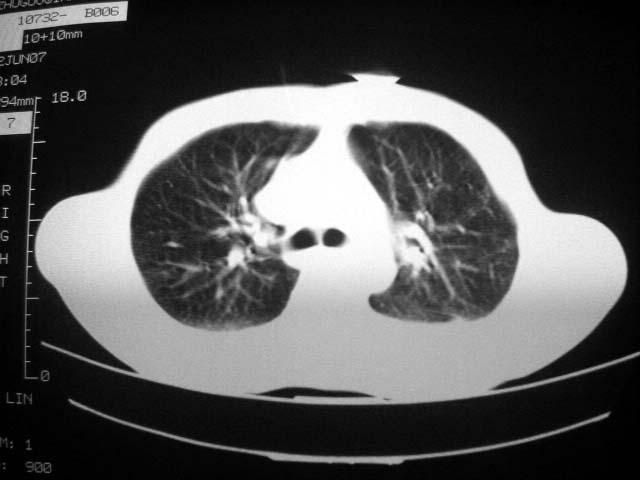

标题: CT7988D:近期图像 出乎意料!

从ct7988c 至今未用任何抗生素及抗痨药,维持保肝治疗。患者低热、咳血渐消失。

07年6月22号复查

前几次大家认为是转移癌,但此次复查病灶却明显吸收好转,不支持诊断。请大家讨论。[emb10]